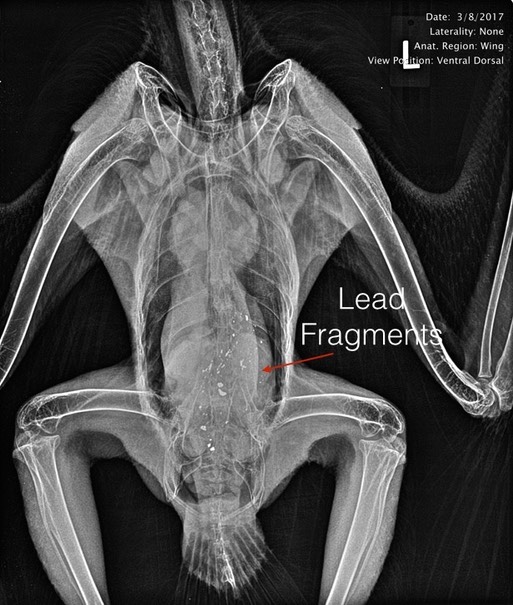

A subadult Bald Eagle was admitted this past week. She was found in the mountains west of La Grande, OR. Her blood lead level was 385 micrograms/deciliter. A radiograph showed she still had many fragments of lead in her digestive tract. We were unsuccessful in removing the lead from her gut and the eagle died the day after admission. She acquired the lead by eating an animal that had been shot with lead ammunition. This is why we support hunting with non lead ammunition.